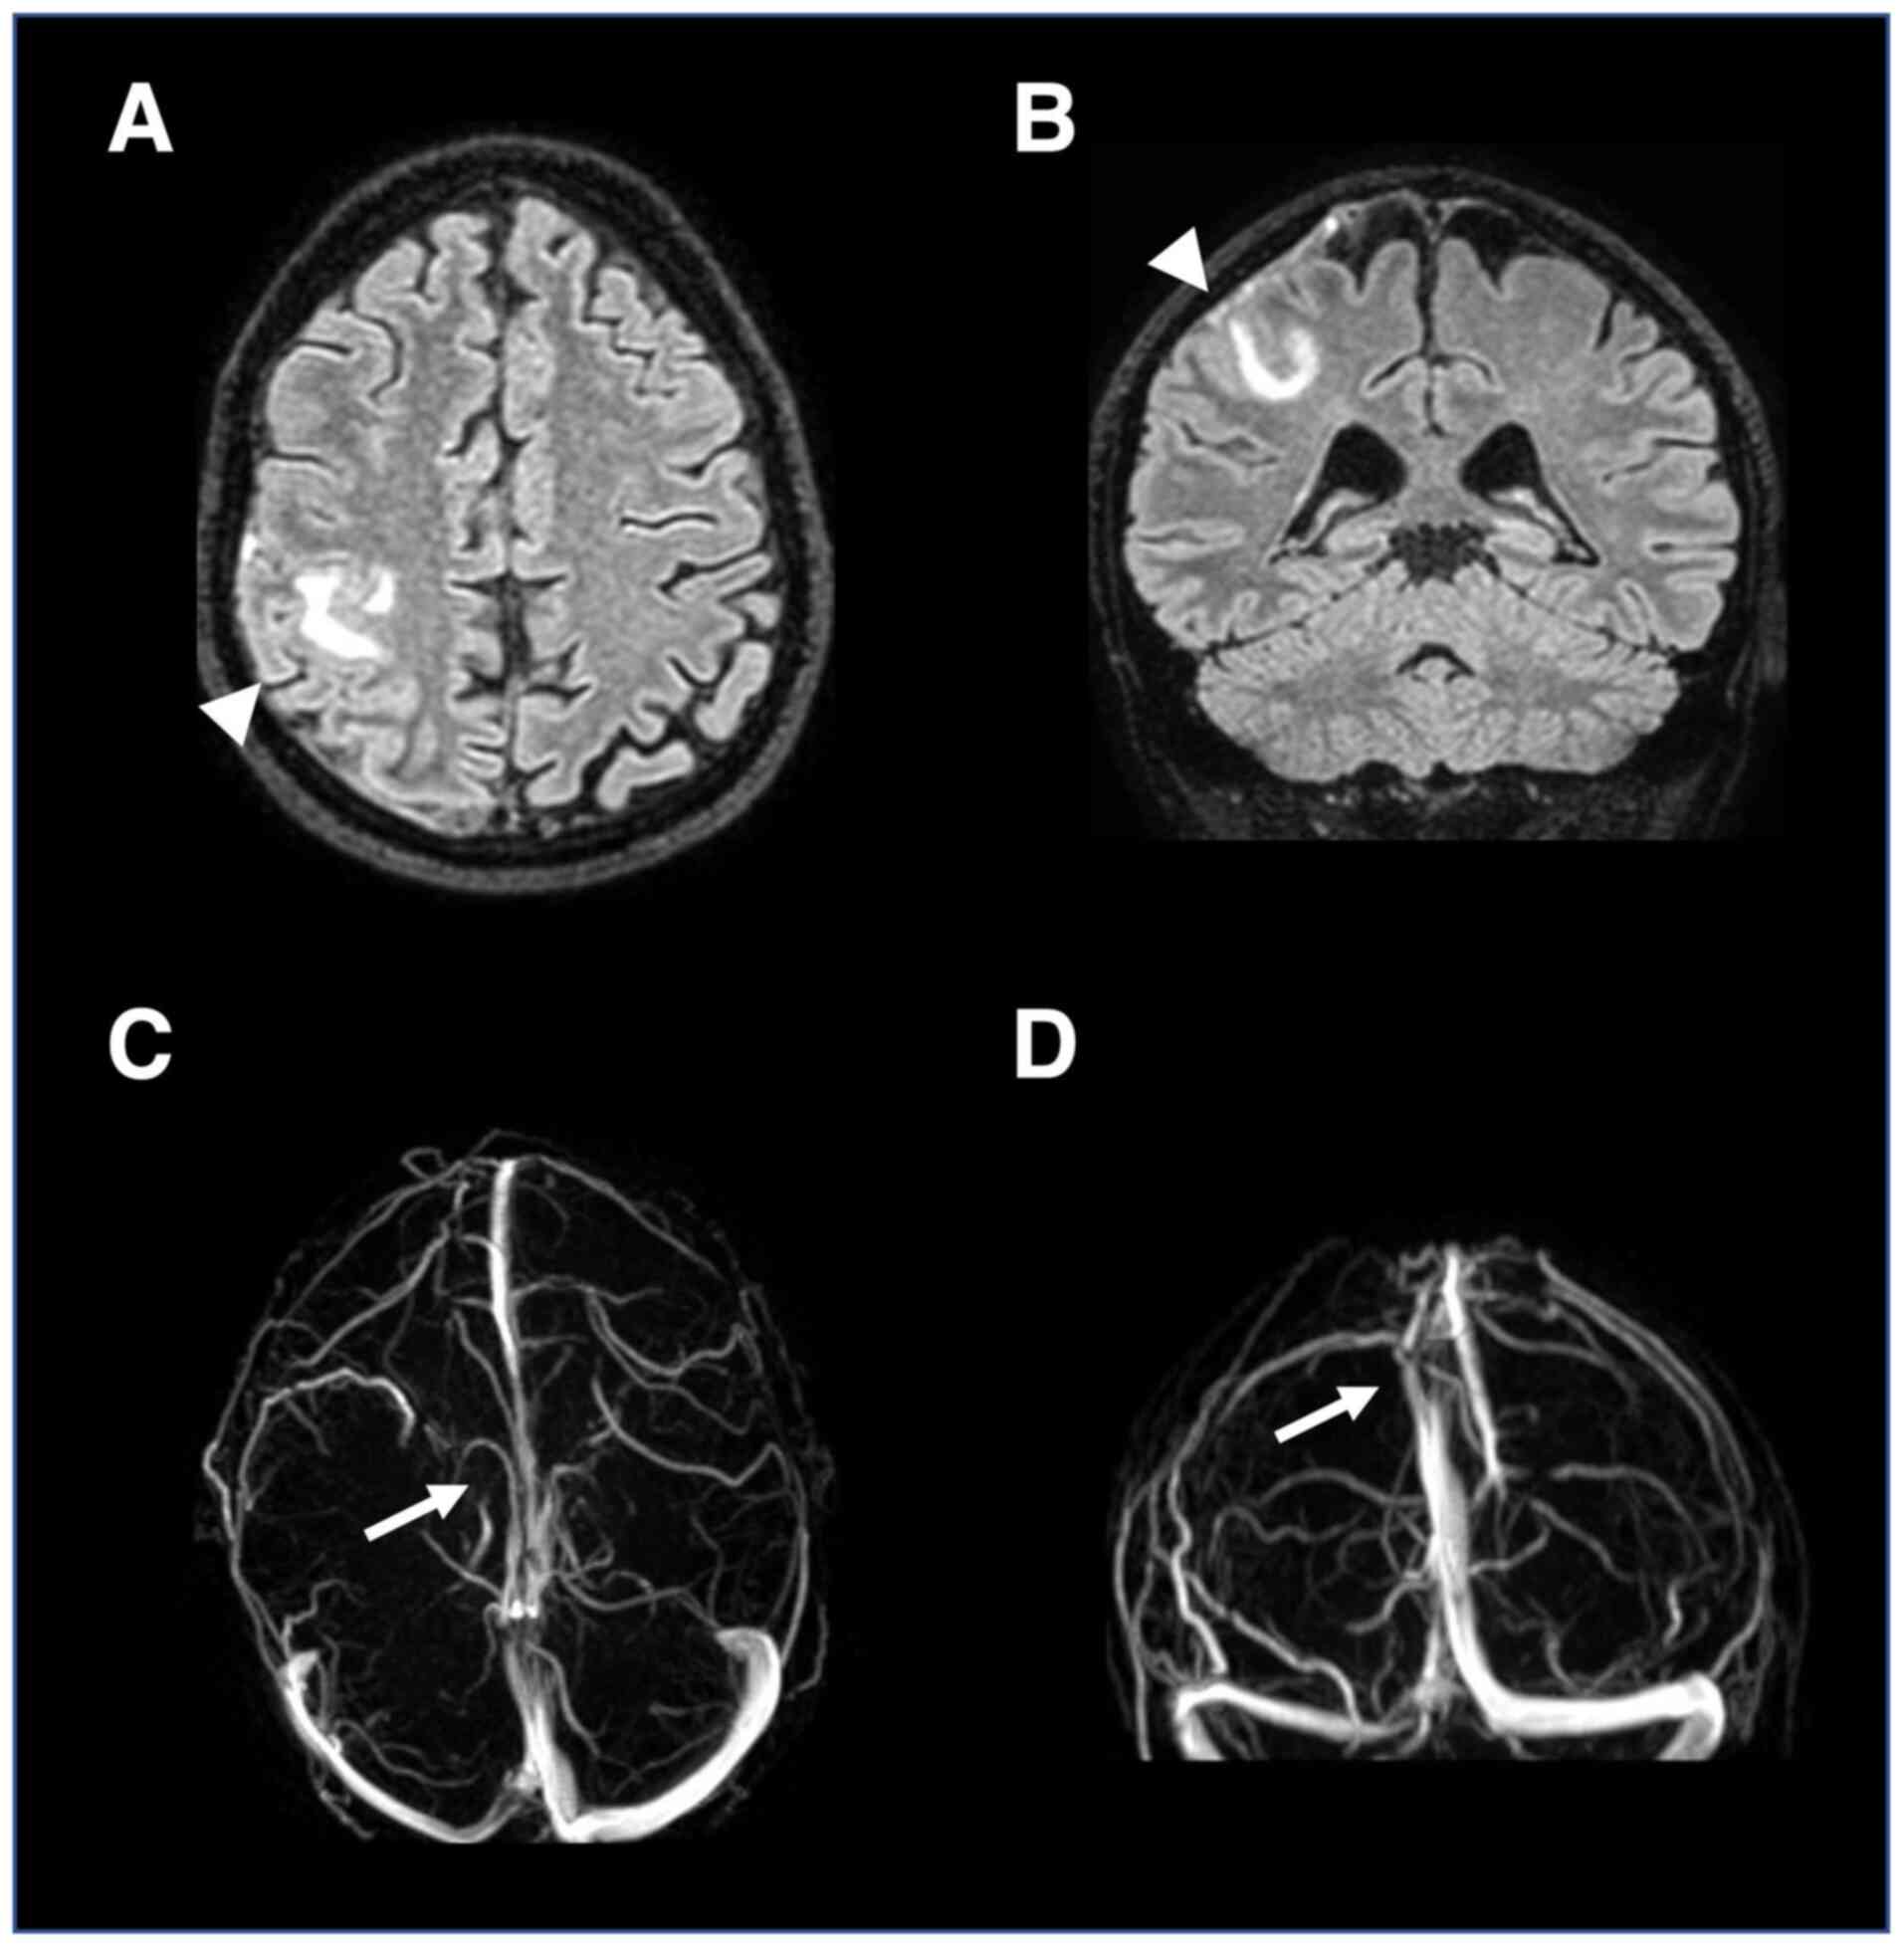

Figure 1

Spine magnetic resonance imaging. Hyperintense cervical cord lesions (arrows) in short-TI inversion recovery sagittal sequences.

A healthy, 37-year-old man who was a non-smoker presented to the Neurology Unit of ‘Bianchi-Melacrino-Morelli’ Hospital (Reggio Calabria, Italy) with a 2-week history of asthenia, gait difficulties, numbness of the lower limbs and urinary urgency. There was no history of recent vaccination, fever or systemic infections. Neurological examination revealed sensory ataxia, brisk tendon reflexes in all four limbs and hypoesthesia extending from the thoracic region (corresponding to the C5 sensory level) to the lower limbs. An urgent spinal magnetic resonance imaging (MRI) scan (Fig. 1) showed a T2- and short-TI inversion recovery-hyperintense, continuous cord lesion from C2 to T1, without contrast enhancement (CE), consistent with longitudinally extensive myelitis (LETM). Additional multiple smaller dorsal cord hyperintensities showed CE, whereas brain and orbital MRI findings were normal. Blood tests revealed mild neutrophilic leukocytosis. A broad infectious and autoimmune work-up, including a COVID-19 test and antinuclear antibodies, was unremarkable. Cerebrospinal fluid (CSF) analysis of a specimen from a lumbar puncture (LP) revealed elevated protein levels (100 mg/dl; normal value, <43 mg/dl), with normal leukocyte count, CSF/serum albumin ratio and glucose levels. The CSF-Film Array assay was performed by the Department of Pathology of ‘Bianchi-Melacrino-Morelli’ Hospital and was negative for common infectious agents. No intrathecal-restricted synthesis of IgG oligoclonal bands was detected in the CSF. Serum anti-MOG antibodies, tested by the Department of Pathology of ‘Bianchi-Melacrino-Morelli’ Hospital using a fixed cell-based assay, were positive at a titer of 1:100, whereas antibodies against AQP4 in both CSF and serum were absent.